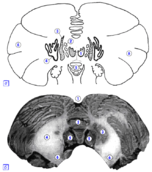

На рисунке: А. 1 – ядро шатра, 2 – шаровидное ядро, 3 – пробковидное ядро, 4 – зубчатое ядро, 5 – червь мозжечка, 6 – полушарие мозжечка. Б. 1 – задняя вырезка мозжечка, 2 – червь мозжечка, 3 – зубчатое ядро, 4 – мозговое ядро, 5 – миндалина, 6 – средняя ножка.

По обеим сторонам червя идут продольные бороздки, на передней — более мелкие, на задней — более глубокие, которые отделяют червя от полушарий мозжечка. Серое вещество образует кору мозжечка (cortex cerebelli) и его ядра. В коре мозжечка различают 3 слоя: молекулярный слой (stratum moleculare), промежуточный - ганглиозный (stratum ganglionare) и зернистый слой (stratum granulosum). Ядра мозжечка (nuclei cerebelli) представляют собой парные скопления серого вещества в толще мозгового тела, corpus medullare. Различают следующие ядра:

1. Ядро шатра, nucleus fastigii, располагается в белом веществе червя, по обеим сторонам его серединной плоскости, под долькой язычка и центральной долькой, в крыше четвертого желудочка.

2. Шаровидное ядро, nucleus globosus, залегает несколько медиальнее пробковидного ядра и на разрезе может быть представлено в виде нескольких небольшой формы шариков.

3. Пробковидное ядро, nucleus emboliformis, располагается медиально и параллельно зубчатому ядру.

4. Зубчатое ядро, nucleus dentatus, залегает в медиально-нижних участках белого вещества. Это ядро представляет собой волнообразно изгибающуюся пластинку серого вещества с небольшим перерывом в медиальном отделе, который получил название ворот зубчатого ядра, hilus nuclei dentati.